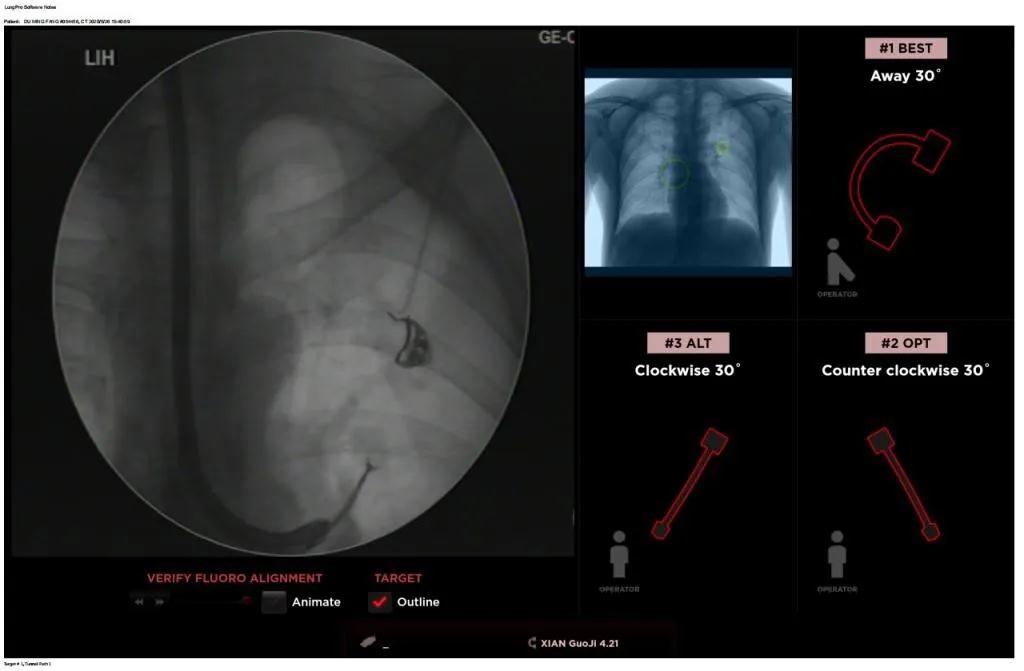

西安國際醫(yī)學中心醫(yī)院呼吸內(nèi)科完成西北地區(qū)首例LungPro全肺導航系統(tǒng)引導下BTPNA手術

近日,西安國際醫(yī)學中心醫(yī)院胸科醫(yī)院歐陽海峰副院長完成西北地區(qū)首例LungPro全肺導航系統(tǒng)引導下經(jīng)支氣管鏡跨肺實質(zhì)肺外周結節(jié)活檢術。

經(jīng)過充分的討論后,歐陽海峰副院長決定為患者實施LungPro全肺導航系統(tǒng)引導的經(jīng)支氣管跨肺實質(zhì)肺外周結節(jié)活檢術。Broncus導航系統(tǒng)LungPro具有全球領先獨創(chuàng)的BTPNA技術(支氣管鏡下跨結節(jié)抵達術),可以實現(xiàn)對氣道外周孤立性肺小結節(jié)的精準定位,建立直接通往氣道外病變部位的通道,以實現(xiàn)全肺的診斷及后續(xù)治療。這項技術不僅彌補了現(xiàn)有支氣管鏡技術由于受限于病變部位是否有氣道可通向以及無法準確定位病變部位而造成的較低診斷率,同時還彌補了CT引導下經(jīng)胸穿刺(TTNA)無法適用于某些特定部位如中央及肩胛骨等結節(jié)的問題,并且還避免了經(jīng)胸穿刺給患者帶來氣胸、出血的高風險,可有效提高肺部結節(jié)及早期肺癌診斷陽性率,亦可用于早期肺癌的射頻消融或微波治療,具有微創(chuàng)、安全、同期雙肺診療等優(yōu)勢。

BTPNA技術整合了虛擬導航支氣管鏡VBN、氣道內(nèi)超聲rEBUS、TBNA、高壓球囊擴張、X線輔助等多項三、四級呼吸內(nèi)鏡技術。歐陽海峰副院長有3000 TBNA、1000 rEBUS、500 VBN、800 球囊擴張方面的技術積累,10年來個人每年完成三、四級呼吸內(nèi)鏡手術1200余例,這有效保障了BTPNA技術的順利開展。

團隊術前進行了精心的準備,通過高分辨率CT建立了導航路徑,在麻醉科手術室的配合下,借助LungPro引導順利的確定了病灶部位、建立隧道并實施活檢,術后患者恢復順利出院。